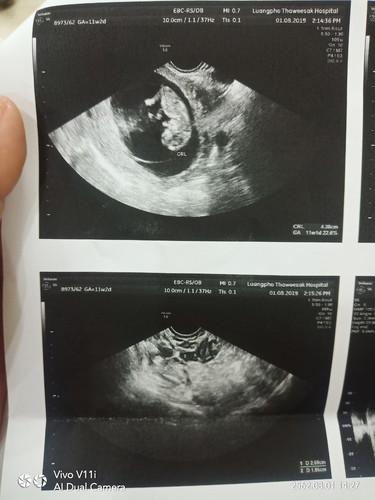

วันนี้เลือดออกสองรอบแล้ว ไปหาหมอมาเมื่อตอนเที่ยง หมอบอก เสี่ยงแท้งคุกคาม? แต่อัลต้าร์ซาวตัวเล็กดิ้นดี หัวใจยังเต้นอยู่ แต่หมอลงท้ายด้วยว่า มีสิทธิ์แท้งแค่ตอนนี้ปากมดลูกไม่เปิด คือเรามีสิทธิ์จะเสียลูกไปหรอคะ